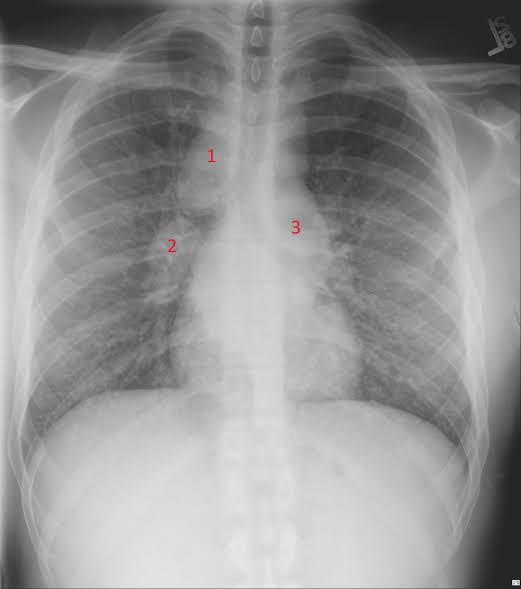

Straight forward

Patient complaints of cough,rash and joint pains.

What is this sign and diagnosis?

#MedTwitter #MedX #MedEd #CardioTwitter #GITwitter #FOAMed @albertoortegana @TSM_Humanist @drsthanus @IhabFathiSulima @esanum @mendietaalex1 @MEmwanta @daoo100 @PJaseja

What’s your differential diagnosis?| Medical | medicine | USMLE

#medical #medicine #usmle